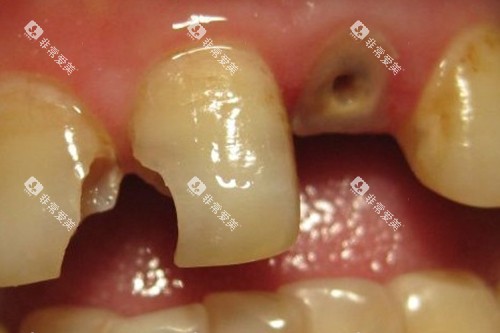

补牙是口腔科常见的治疗项目之一。

如果牙齿出现龋齿,就需要及时补牙。

娄底市中心医院口腔科根据补牙材料的不同,收费也有所差异。

普通树脂补牙材料价格相对较为亲民,每颗牙齿的收费在 200 - 300 元左右。

这种材料具有较好的耐磨性和美观度,能够满足大多数患者的需求。

如果选择进口的高端树脂补牙材料,其收费会相对较高,每颗牙齿大约在 400 - 600 元。

这类材料在颜色、硬度和粘结性等方面表现更为出色。